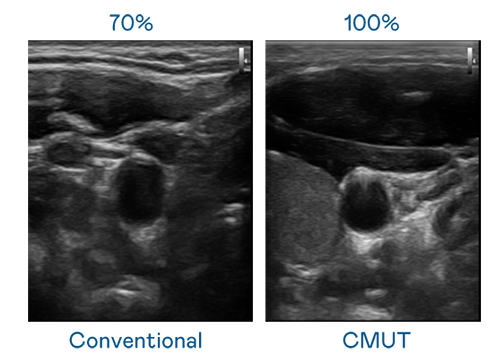

CMUT 技术是一种用电容式微机电元件来产生超音波讯号的技术。与传统 PZT 压电式技术相比,CMUT 频宽增加 30%,更宽频的超音波讯号让影像解析度大幅提升,是实现高影像品质医疗超音波扫描、促进精准医疗发展的关键技术。

超音波影像的解析度高低,首先取决于探头能发出的讯号频宽。AG贵宾会 CMUT 可提供高清晰的超音波讯号,提供高频宽、高灵敏度、影像纹理细节更高的超音波影像,协助医护人员缩短影像判读时间及利用精准的医疗影像进行诊断。